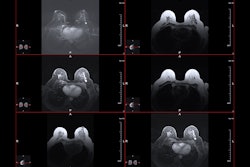

Protocol time and recall bounds as a function of AI specificity and sensitivity. On the top, the bounds are shown as a function of the specificity of the AI algorithm, for a fixed value of the sensitivity of that same AI model. On the bottom, the bounds are shown as a function of the sensitivity, for a fixed specificity. Graphics and caption courtesy of the ISMRM.